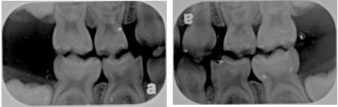

3. Dental radiographs -- Depending on your child’s age and level of cooperation, the dentist may prescribe some dental x-ray that allows her to view the structure of the jaw, the position of any teeth that have not yet erupted, malformed roots, and tooth decay.

4. x-ray x-ray